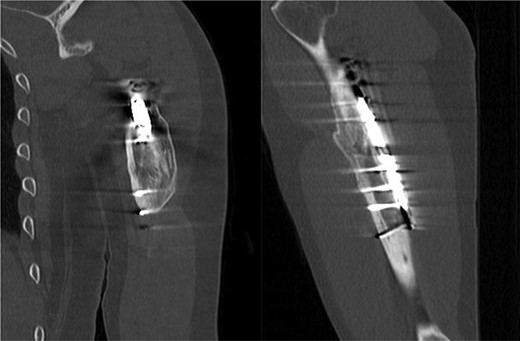

ML is a 52-year-old male who presents to our clinic complaining of severe left anterolateral arm pain after being involved in a motor vehicle accident 10 years prior to presentation. At that time, he had suffered a left mid-shaft humerus fracture treated with open reduction and internal fixation, as well as a traumatic brain injury and multiple other injuries to the right lower extremity resulting in the below-knee amputation. For the last several years he has had severe pain in the anterolateral aspect of the left arm, but denies any weakness or parasthesias. On physical examination, he demonstrates localized tenderness to palpation along the anterolateral aspect of the mid-humerus ~8–10 cm proximal to the lateral epicondyle. The patient had full motor function, though somewhat limited by pain, and sensation was intact to light touch throughout the radial nerve distribution. Plain films (Fig. 1) and CT-imaging (Fig. 2) show a healed fracture with acceptable alignment and hardware in good position. The patient elected to undergo lidocaine injection at the site of maximal tenderness, which gave excellent, albeit temporary pain relief, for about a week. Electrodiagnostic studies obtained at that time revealed chronic radial nerve neuropathy above the spiral groove.

CT, coronal/sagittal showing a healed mid-shaft humerus fracture.